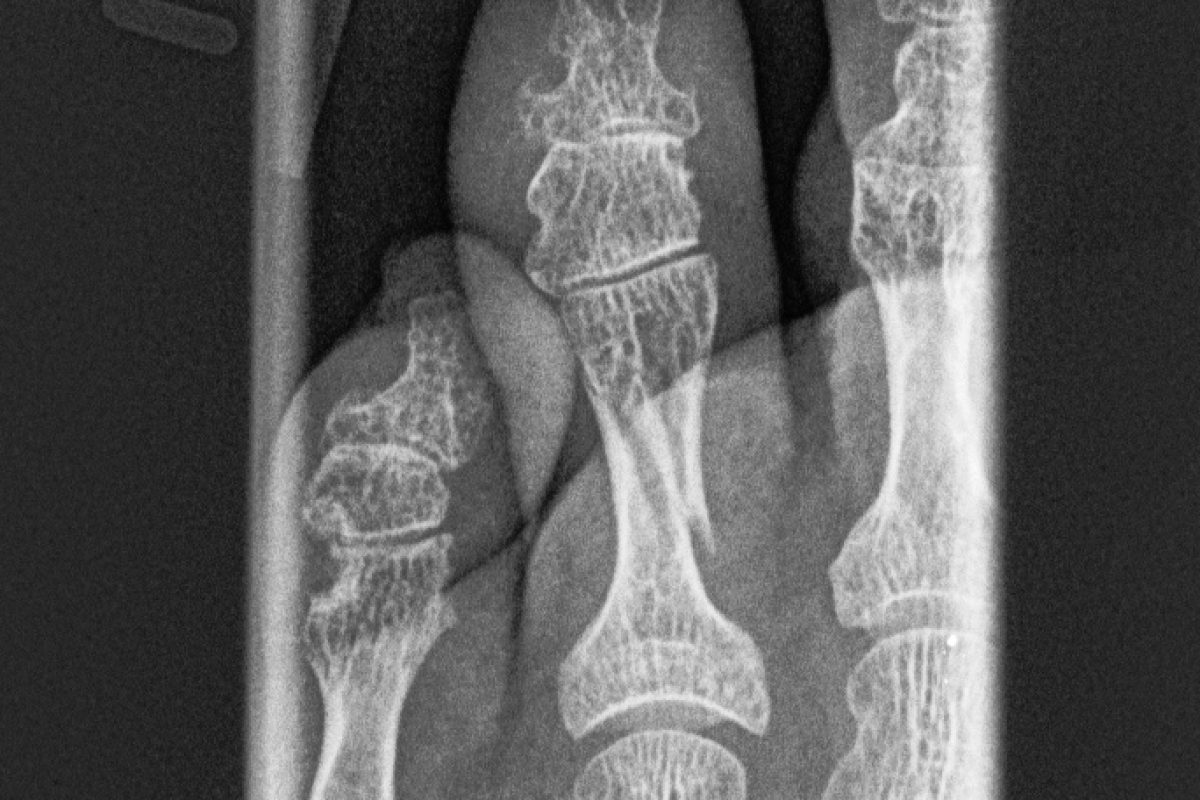

Moin, püppchen hat sich vorhin den zeh an der vorderpfote ganz innen gebrochen, beim abtasten merkt man die sich verschiebenden knochenstücken (2 große, kleinere fühle ich nicht) und es knackt wenn sie läuft. Der zeh ist zu zersplittert und kann nich mit platte bzw draht so fixiert werden, dass der hund dauerhaft beschwerdefrei laufen kann. Ursachen und diagnose meist liegt die ursache für einen beinbruch beim hund in einem unfall, der mit hohen aufprallgeschwindigkeiten verbunden ist.

Vor 2 1/2 Jahren Habe Ich Die Pfote Mal Röntgen Lassen Da Die Zehen Ja Anders Belastet Werden Als Bei Einer Normalen Pfote Und Man Mal Irgendwann, Sollte Es Mal Probleme Geben, Vergleichen Und Eine Veränderung Besser Erkennen Kann.